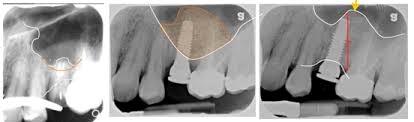

После утраты верхних жевательных зубов исчезает нагрузка на опорную костную ткань верхней челюсти и, расположенная над ними воздушная камера, особенно со временем, заполняет собою освободившиеся от корней зубов пространства.Этот процесс пневматизации фиксируется врачом хирургом при диагностическом рентгенологическом обследовании на разных стадиях его развития.Удаление верхних жевательных зубов запускает процесс резорбции, т.е. происходит убыль объема костной ткани в результате прекращения функционирования кости, а именно, поддержки зубного корня.Отсутствие жевательной нагрузки на поверхности боковых зубов верхней челюсти, вследствие адентии, является причиной развития атрофии костной ткани челюсти, иными словами, уже через три месяца после удаления зуба, начинается прогрессирующее уменьшение высоты и ширины альвеолярного отростка.Недостаточная толщина опорной кости создает неблагоприятные условия для установки и надежного удержания имплантата.Данный клинический случай затрудняет использование дентальных имплантатов для восстановления дефектов зубного ряда и является показанием для проведения синус-лифтинга верхней челюсти.Имплантация зубов в условиях показанных к проведению синус-лифтинга верхней челюсти, но не произведенного, будет физиологически тканью остеоинтегрирована, но при положении шейки имплантата вровень с альвеолярным краем неизбежно прободение пазухи и перфорация Шнейдеровой мембраны, что в длительной перспективе, осложнит эксплуатацию конструкции имплантат-абатмент-коронка зиянием верхушки имплантата в придаточную носовую пазуху.Даже при самом высоком уровне индивидуальной гигиены конструкции со стороны полости рта, обнаженная верхушка, открытая во внешнюю воздушную среду придаточной пазухи носа, неизбежно будет осеменена микрофлорой носовой полости.В этой ситуации она становится слабым звеном, при возникновении воспаления, она невозможна к сервису, неисполнима гигиена данного участка не хирургическими методами.Применение остеопластики делает возможным восстановление утраченного количества костной ткани, и тем самым, является подготовительным этапом перед имплантацией зубов.Существуют и другие причины, способствующие костным изменениям, которые исключают возможность прочного установления имплантата:-атрофия костной ткани наступает естественным образом с возрастными изменениями-утоньшение костной ткани происходит вследствие долгого использования протезов, которые не воспроизводят необходимую жевательную функцию.

На ранних стадиях возможно использование коротких имплантатов. Пограничным случаем можно считать наличие объема костной ткани с линейным размером высоты 7 мм, так как некоторые фирмы производители предлагают укороченные серии имплантатов длиной 6 мм.При большей пневматизации показан закрытый синус лифтинг или мягкий (soft) с доступом через канал ложа имплантата.При имеющемся объеме костной ткани менее 5 мм показан открытый синус лифтинг - пластика дна верхнечелюстной пазухи с доступом-перфорацией передней стенки пазухи.При расстоянии между кортикальными пластинками дна пазухи и вершиной альвеолярного отростка менее 3 мм, трофическая функция костной ткани не сможет обеспечивать регулярное снабжение пластическими элементами, клетками, сформировать полноценное кровоснабжение, необходимые для ремодулирования материала, его оссификации в полном объеме, окостенении и формированиия прочностных свойств необходимых для выполнения жевательной нагрузки.